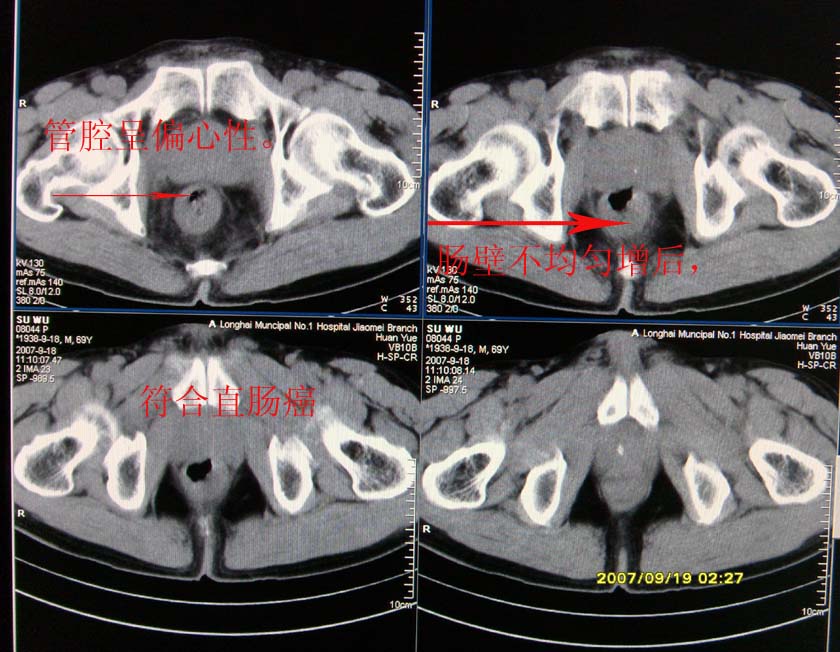

以下是引用xclzq_910在2007-9-19 16:58:00的发言:[br]直肠壁增厚,管腔偏移,直肠癌可能性大

以下是引用宝天曼在2007-9-19 21:11:00的发言:[br]根据直肠壁不规则增厚,考虑直肠肿瘤,不过最后的确诊还是需要肠镜.